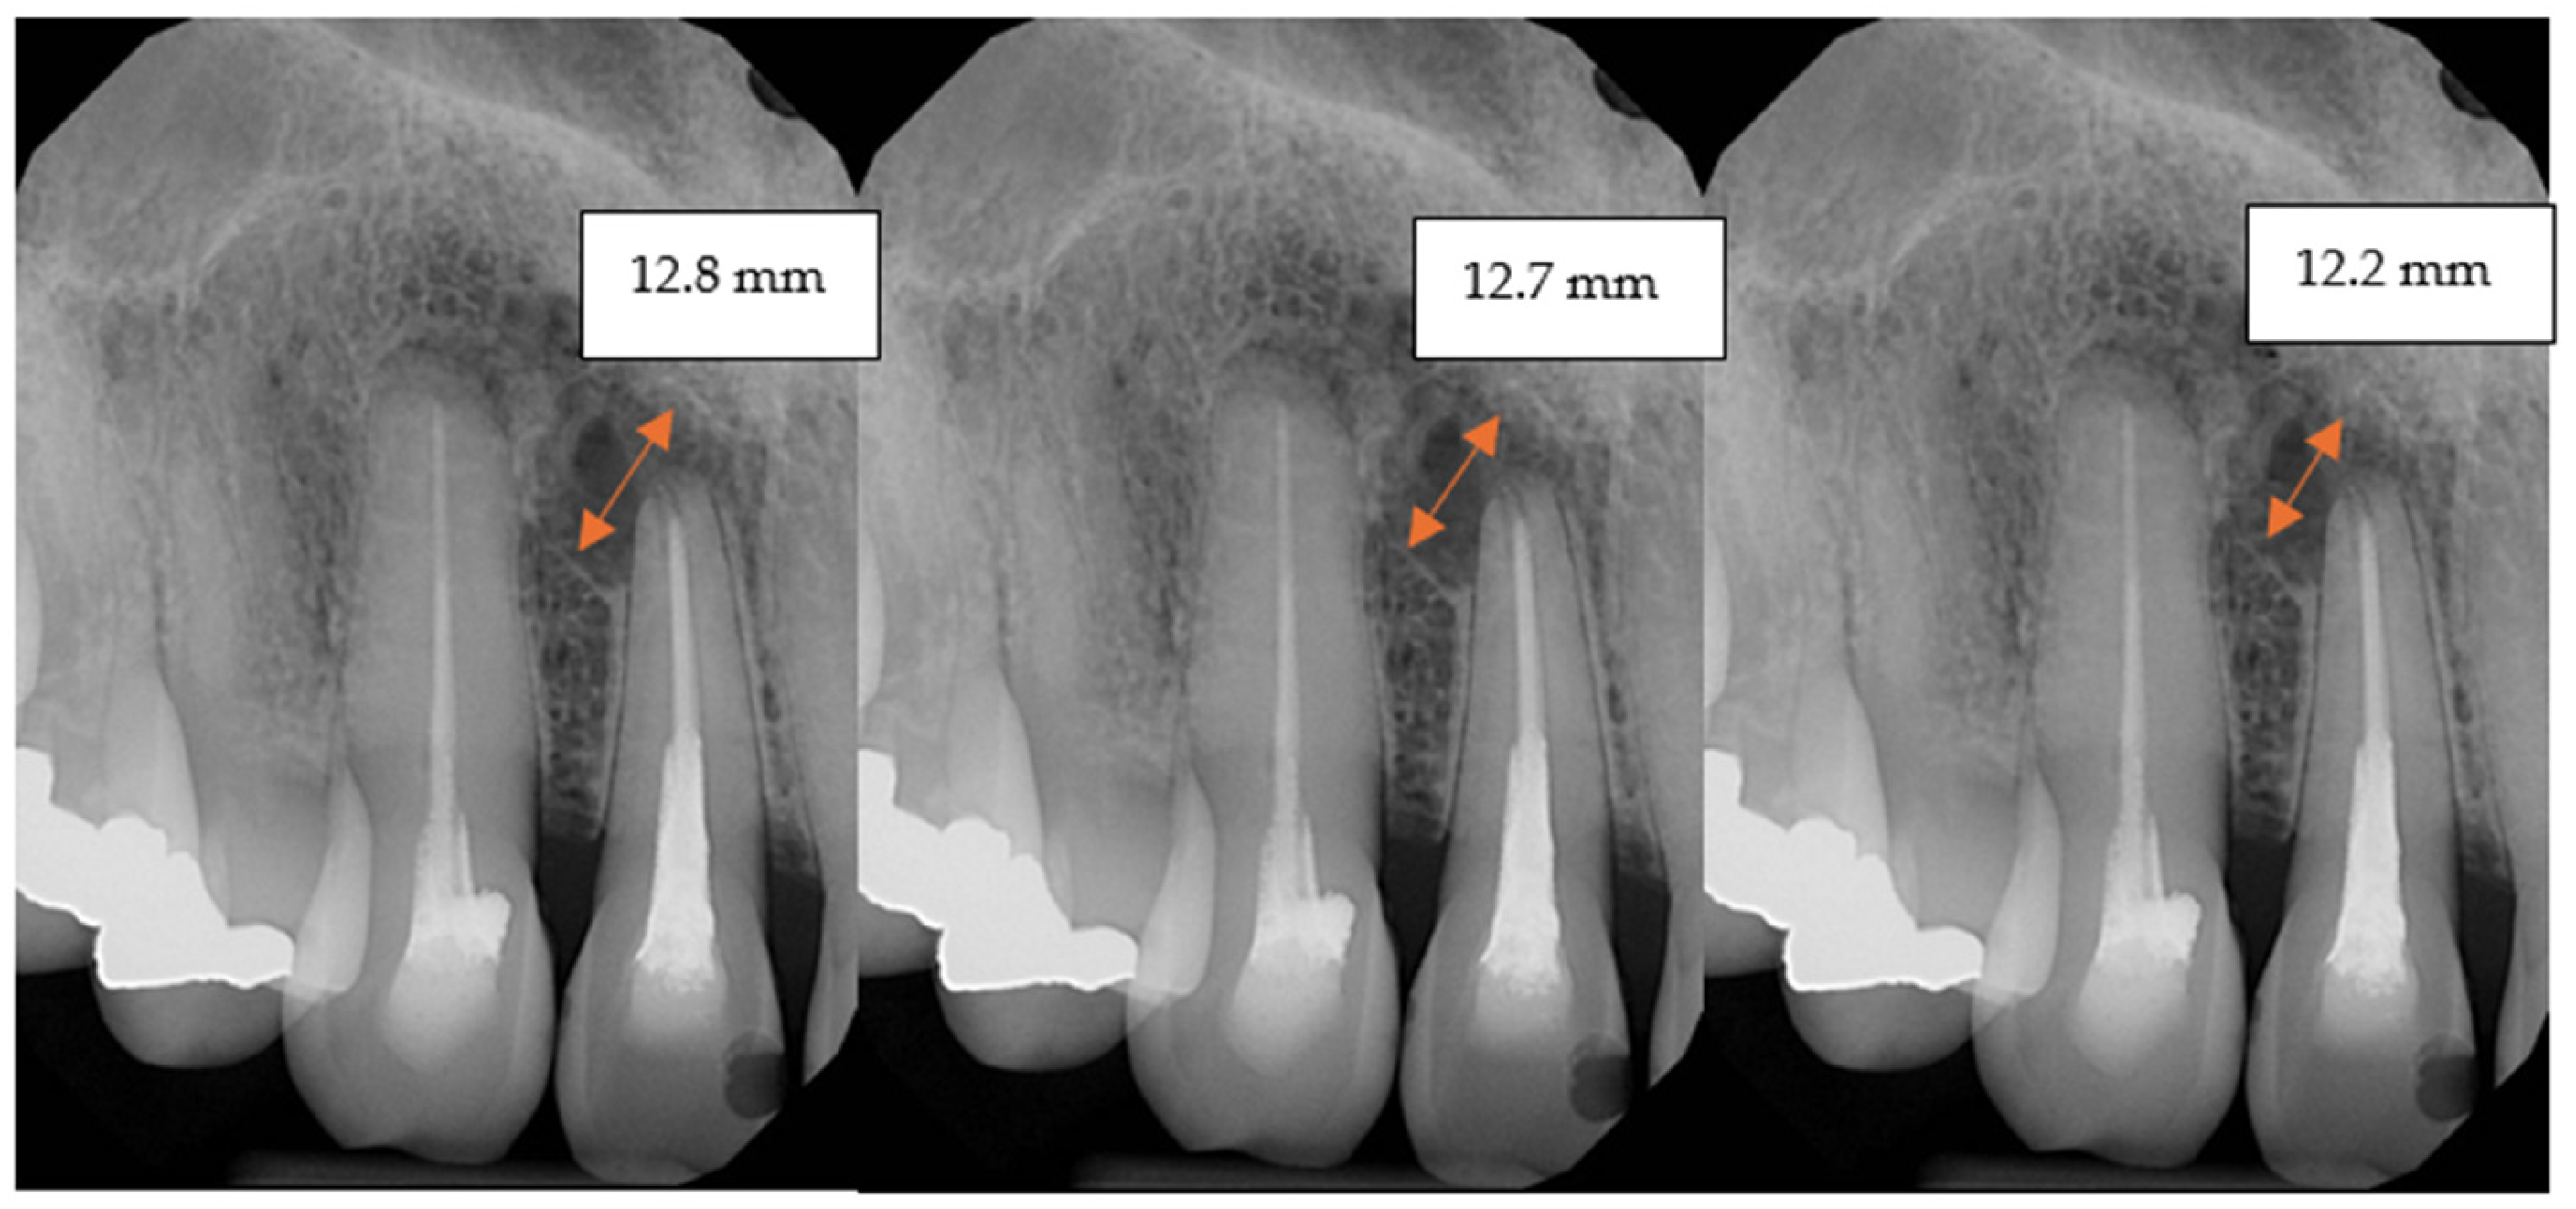

| Postoperative (mean mm ± SD) | 17.97 ± 4.98 | 18.4 ± 6.56 |

| 6-month follow-up (mean mm ± SD) | 16.69 ± 4.53 | 18.11 ± 6.53 |

| 12-month follow-up (mean mm ± SD) | 15.23 ± 3.67 | 17.66 ± 6.52 |